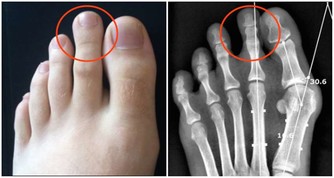

5、頭暈、乏力、嗜睡: 甲醛可影響人的造血系統,輕則引發貧血,嚴重的甚至可能導致白血病。有調查指出,醫院血液科病房中三成以上白血病患者的家庭在兩年內進行過裝修。而兒童因裝修患病的機率更高,佔患病兒童的半數以上。當人體血液供應不足時,就會經常感到疲憊,走路都沒有力氣。因此,入住新居後有頭暈、乏力、嗜睡的症狀,應及時去醫院檢查血常規。